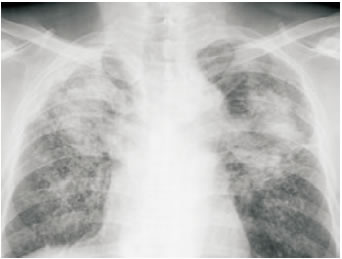

大容量的肺灌洗就是通常所說的洗肺。在身體全麻的狀態(tài)下,醫(yī)生將一個(gè)Y型的管倒插入肺中,一側(cè)進(jìn)入右肺,一側(cè)進(jìn)入左肺。灌洗過程中,右側(cè)肺由機(jī)器進(jìn)行呼吸運(yùn)動(dòng),左側(cè)則灌入灌洗液進(jìn)行洗肺,這樣做的目的是達(dá)到氣、水分離。灌洗液要高于患者50cm,引流瓶低于患者60cm,所有的灌洗液都放在恒溫下以待使用。直到灌洗液澄清為止,灌洗才算結(jié)束。根據(jù)醫(yī)生的臨床記錄,多數(shù)礦工引流出來的液體呈現(xiàn)黑色,陶瓷工引流出來的是的液體為白色。

洗肺之后引流出來的灌洗液(圖片來自網(wǎng)絡(luò))

洗肺可以顯著減輕塵肺病患者的痛苦。洗肺之后遠(yuǎn)離粉塵來源的話,可以不用再次進(jìn)行洗肺。但是如果洗肺之后,仍然回到了高濃度高危害的工作環(huán)境中,那就不得不進(jìn)行第二次洗肺了。